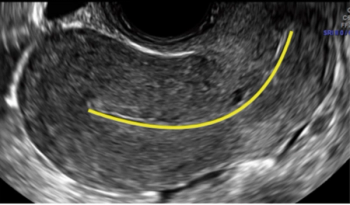

Tackling the difficult IUD insertionBySigrid Tristan, MD, MSc,Amna Dermish, MD, MScJune 21st 2018The goal of this article is to review these challenges and the evidence behind measures to address challenging IUD insertions.